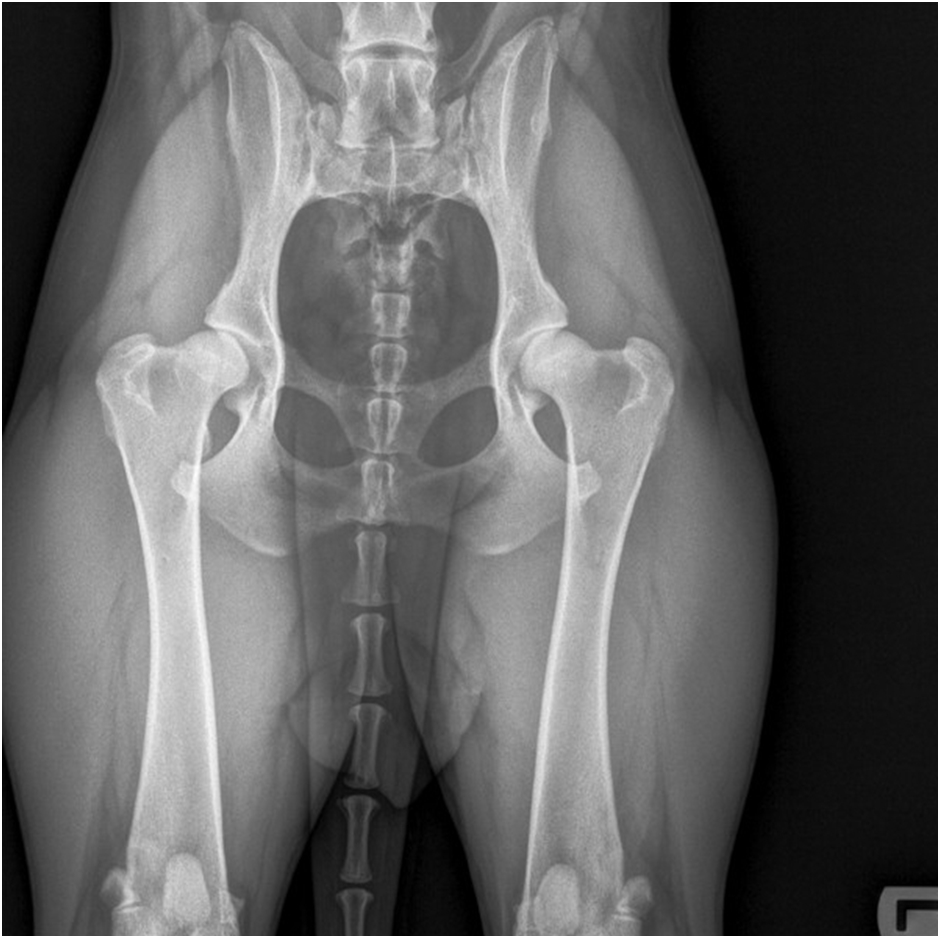

Wenn Hüftkopf und Hüftpfanne nicht richtig zusammenpassen, liegt eine Hüftdysplasie vor, d. h. das Hüftgelenk ist dann nicht richtig ausgebildet. Bei einer Hüftdysplasie ist der Abstand zwischen Kopf und Pfanne zu groß, was zu Arthrose (Gelenkverschleiß) führt. Der Knorpel verliert an Qualität, die Gelenkschleimhaut entzündet sich (Arthritis) und um das Gelenk herum kommt es zum Knochenumbau. Diese Osteoarthritis verursacht auch Schmerzen. Unten sehen Sie eine Röntgenaufnahme der Hüfte eines Dobermanns mit schwerer Hüftdysplasie, insbesondere am rechten Hüftgelenk (HD E).

Schwere Hüftdysplasie rechts